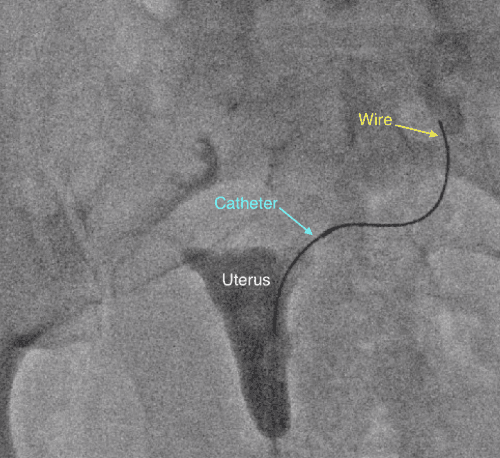

During the procedure, similar to a pelvic exam at your OBGYN, you lay on your back and a speculum is placed into the vagina. Then a small catheter is inserted through the cervix and a contrast agent, or dye, is injected into the uterus so an X-ray image of the uterine cavity can be obtained. When a fallopian tube blockage is identified, another smaller catheter and wire are threaded into the fallopian tube to open the blockage.

Our outpatient center sees patients that travel from not only the Los Angeles area but throughout the West Coast seeking our specialists’ expertise. The procedure is performed by our Interventional Radiologist who is board certified in image-guided procedures using X-rays, tiny catheters and other micro-tools. What is Interventional Radiology? This is the only specialty in medicine specifically trained to perform image-guided minimally invasive procedure. Read more here.